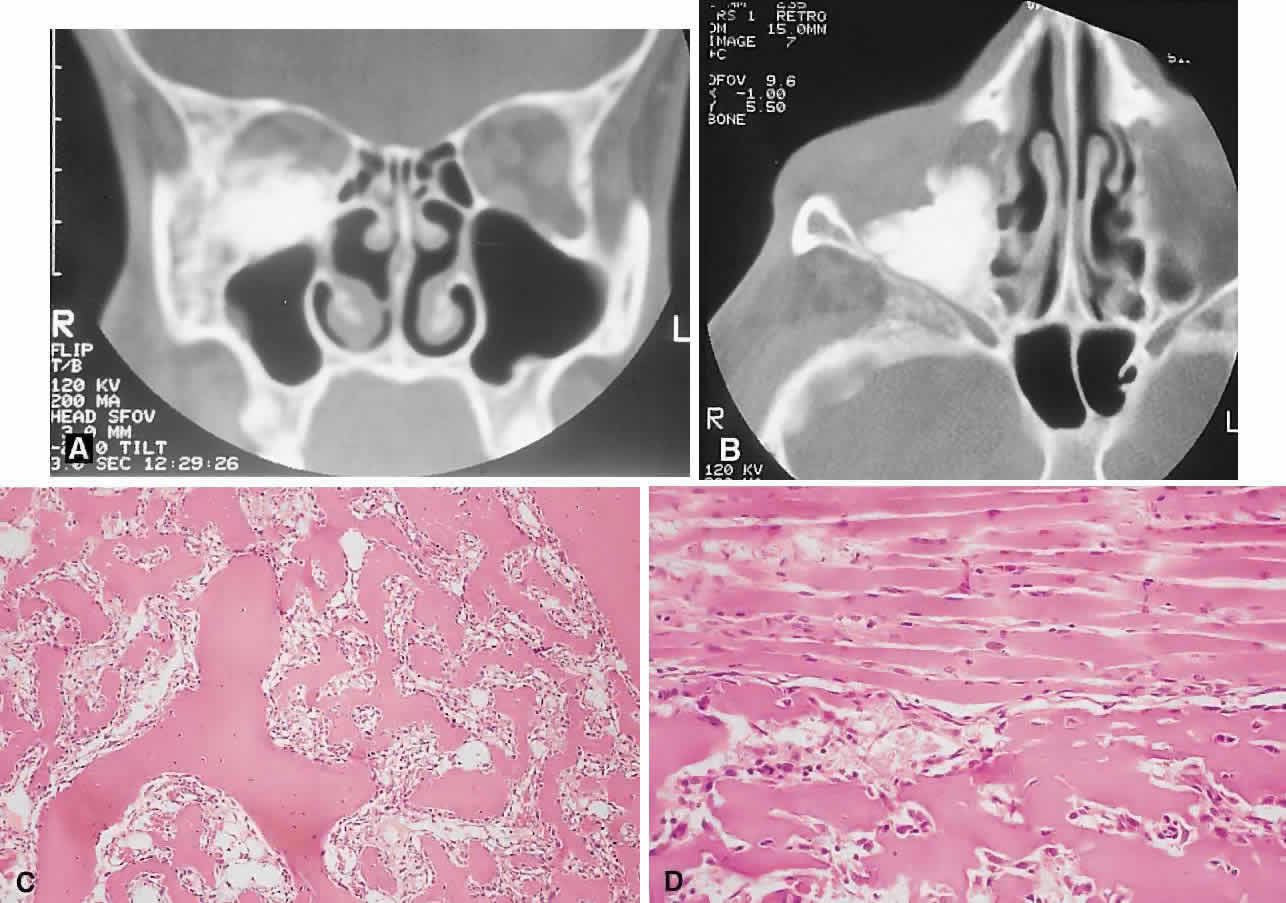

PRESENTATION. The site and the extent of disease are the major determinants of symptomatology. Facial asymmetry, proptosis, and globe displacement evolving over many years are the most common manifestations (Fig. 2). Nasolacrimal duct blockage, diplopia, nasal obstruction, malocclusion, raised intracranial pressure, and cranial nerve palsies also occur.25,28–30 Acute or subacute compressive optic neuropathy can arise as a result of intralesional hemorrhage, sphenoidal mucocele, or secondary aneurysmal bone cyst.31 A more chronic visual loss, although less commonly reported, may occur as a result of compression in the optic canal or at the chiasm. On occasion, a superimposed ischemic neuropathy in the context of chronic compression leads to an acute on chronic deterioration in vision.32

Fig. 2. A. A 20-year-old man presented with a longstanding history of left proptosis and facial asymmetry. B and C. Bone window CT scan showed extensive fibrous dysplasia involving the greater wing of the sphenoid in a sclerotic fashion and a more pagetoid appearance in the maxillary and ethmoidal regions. D and E. Dominant histologic features consisted of irregular trabeculae of woven bone in a fibrous stroma with minimal osteoblastic activity (E) surrounding the osteoid (hematoxylin-eosin; D × 20, E × 50).

This clinical spectrum is reflected in our experience of 10 cases. Changes in facial contour (7 patients), proptosis (7), globe dystopia (6), and decreased vision (3) were the major signs. Interestingly, seven patients also had pain, either localized to the orbit or described as a diffuse ipsilateral headache.

IMAGING. In the craniofacial bones, fibrous dysplasia tends to expand the bone, with thinning of the overlying cortex. The margins are poorly defined, and the dysplasia transgresses suture lines; the proportion of mineralized to fibrous tissue determines the degree of radiolucency. Most cases demonstrate a relatively equal mixture, resulting in a pagetoid appearance. Where the fibrous element is predominant, there may be cystlike areas; a preponderance of mineralized tissue, however, results in a homogeneous, sclerotic, “ground-glass” picture. Fries34 reviewed 39 patients with fibrous dysplasia of the craniofacial bones and found a pagetoid pattern to be most common (56%), followed by sclerotic (23%) and cystlike (21%) appearances.

HISTOPATHOLOGY. Macroscopically, fibrous dysplasia consists of gritty, white-to-pink tissue, often with blood or serous-filled cystic areas. Histologically, there is a fibrous background containing trabeculae of woven bone. The stroma has variable amounts of collagen, fibroblasts, and vascularity. There may also be myxomatous areas and secondary aneurysmal bone cysts. The curvilinear bone trabeculae take on a variety of configurations, including C or Y shapes (so-called Chinese characters). These trabeculae sometimes have irregular margins as a result of the attachment of collagen fibers arising in the stroma. Cartilaginous nodules as well as small foci of lamellar bone are occasionally seen, but the vast majority of lesions contain immature woven bone. At its periphery, fibrous dysplasia permeates normal bone, and there may be areas of reactive bone with more prominent lamellar bone formation and osteoblastic rimming. Sequential biopsies of fibrous dysplasia from childhood to adult life have shown that the histologic picture does not change with time.36